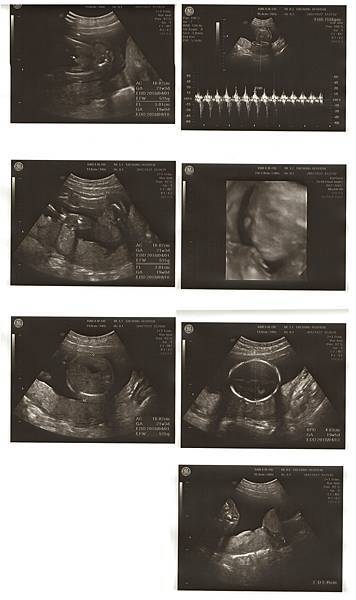

8W3D 9/4回診照心跳,兩週的等待很漫長,到了要照心跳的那天,我和Chris不由自主緊張了起來,也許是上次的經驗讓我們格外緊張與焦慮。一進診間,劉醫師說今天要照心跳喔!

照超音波的時候,醫師一直在肚子上來回滑著儀器,我看著畫面,胚囊明顯變大,但是裡面的東西卻看不清楚,我和Chris開始緊張了起來,躺在診台上的我心臟跳得超快,真的好緊張。

醫師突然請我去廁所把小便解掉,要照陰超看看,還說:照理來說八周應該要有心跳了。聽到這句話的我和Chris整個快無力了~Chris說他當時內心吶喊:不會吧!!

上完廁所後又躺上診台準備照陰道超音波,結果照得好清楚,變大的胚囊裡面已經有胚胎了,劉醫師看著畫面跟我們細心解釋,圓圓的卵黃,是寶寶自己帶的便當,很好喔!

目前大小也在標準值,一邊聽我還是一邊緊張,因為最重要的是我們期待著的心跳聲。接著劉醫師說:來,我們聽聽心跳聲。

“碰碰碰碰碰碰”!好快好有力的聲音,醫師說一分鐘167下,160-180下都是正常的哦!

聽到寶寶心跳聲的當下覺得自己在發抖,也覺得好神奇,肚子裡有了第二個心跳聲。

(看著超音波照片就開始覺得寶寶可愛了)

晚上做第一次產檢,候診的人好多,等到十點多才看診,因為子宮後傾,腹超還是照不清楚,這次一樣照了陰超。

寶寶長大了~!

其實因為上次的經驗,讓我跟Chris每次的檢查都蠻緊張的,結果這次聽到醫生指著照片說:這是他的頭、手、腳⋯的時候,我看見Chris終於露出了笑容(覺得自己小孩很可愛的那種笑容)

看到他這麼開心,真的好幸福。寶寶這次的心跳聲是171,醫生說很正常哦,大小4.22cm也很好~後來我們看照片,原本的10W4D變成了11W1D,預產期日期也提前了~